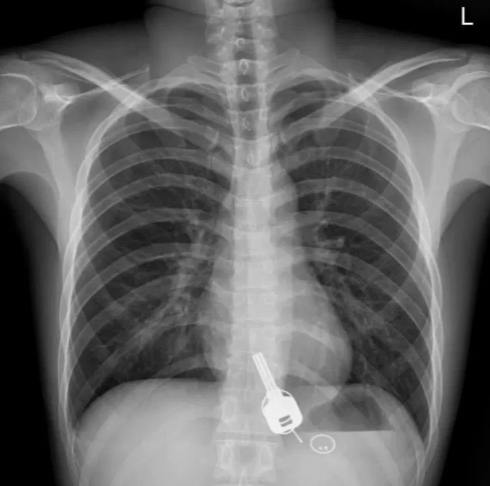

Cuando los médicos realizaron una radiografía de su torso, se sorprendieron al ver lo que parecía una llave alojada en su esófago. Le preguntaron al respecto, y él admitió haber perdido las llaves de su casa la noche anterior, pero no pudo ofrecer ninguna explicación sobre cómo terminaron dentro de su cuerpo. Al parecer se sorprendió tanto como los médicos cuando vio la radiografía.

El personal del Hospital Dongguan analizó la situación y decidió que dejar que las llaves pasaran por el sistema digestivo de Chang, y se eliminaran de forma natural era demasiado arriesgado, ya que el duro objeto podría desgarrar sus intestinos o causar una obstrucción intestinal potencialmente mortal. Al mismo tiempo, tratar de sacarlo con un equipo de endoscopia podría romper su esófago. La tercera opción era una cirugía de emergencia.

Los médicos dijeron que primero intentaron quitar las llaves con un gastroscopio, pero encontraron problemas cuando intentaron extraer la llave a través de la sección más estrecha del esófago de Chang, cerca de la garganta.

La llave era demasiado grande y tirar demasiado fuerte podría haber desgarrado el esófago, lo que habría tenido «consecuencias inimaginables». Así que abortaron el procedimiento y reconsideraron sus opciones. Para empeorar las cosas, la mayoría del personal del hospital estaba fuera de servicio por un feriado nacional, pero afortunadamente un anestesiólogo y el subdirector del Departamento de Gastroenterología del hospital cancelaron sus planes y acudieron para ayudar con la emergencia.

Después que el anestesiólogo le administró a Chang un medicamento que ayudó a relajar sus músculos, un gastroenterólogo pudo extraer la llave de metal y la tarjeta de acceso de plástico del esófago del hombre.